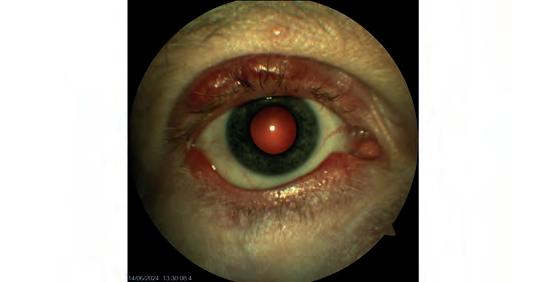

A retinal detachment diagnosed by Queensland optometrist Peter Choc on his Optos Daytona.

A secondary retinal detachment.

Images: Gladstone Vision.